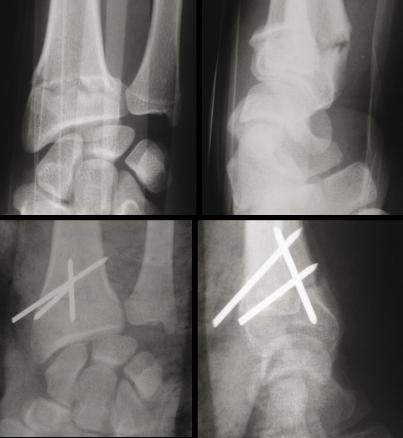

Fracture de Pouteau-Colles : fracture extra-articulaire à déplacement postérieur. (Haut, gauche) Radio de face. (Haut, droite) Radio de profil. Le traitement est parfois orthopédique mais le plus souvent réalisé par brochage percutané. (Bas, gauche) Radio de face. (Bas, droite) Radio de profil.